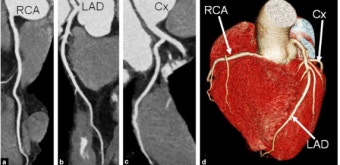

6. 관상동맥석회화 검사란

가장 대표적인 검사는 관상동맥 석회화 CT 검사입니다.

👉 CT로 혈관 속 석회 양을 숫자로 계산해 줍니다.